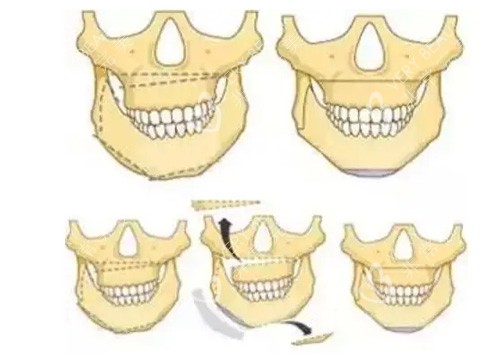

面部不对称的类型

面部不对称的示意图

面部不对称和正常面部的区别